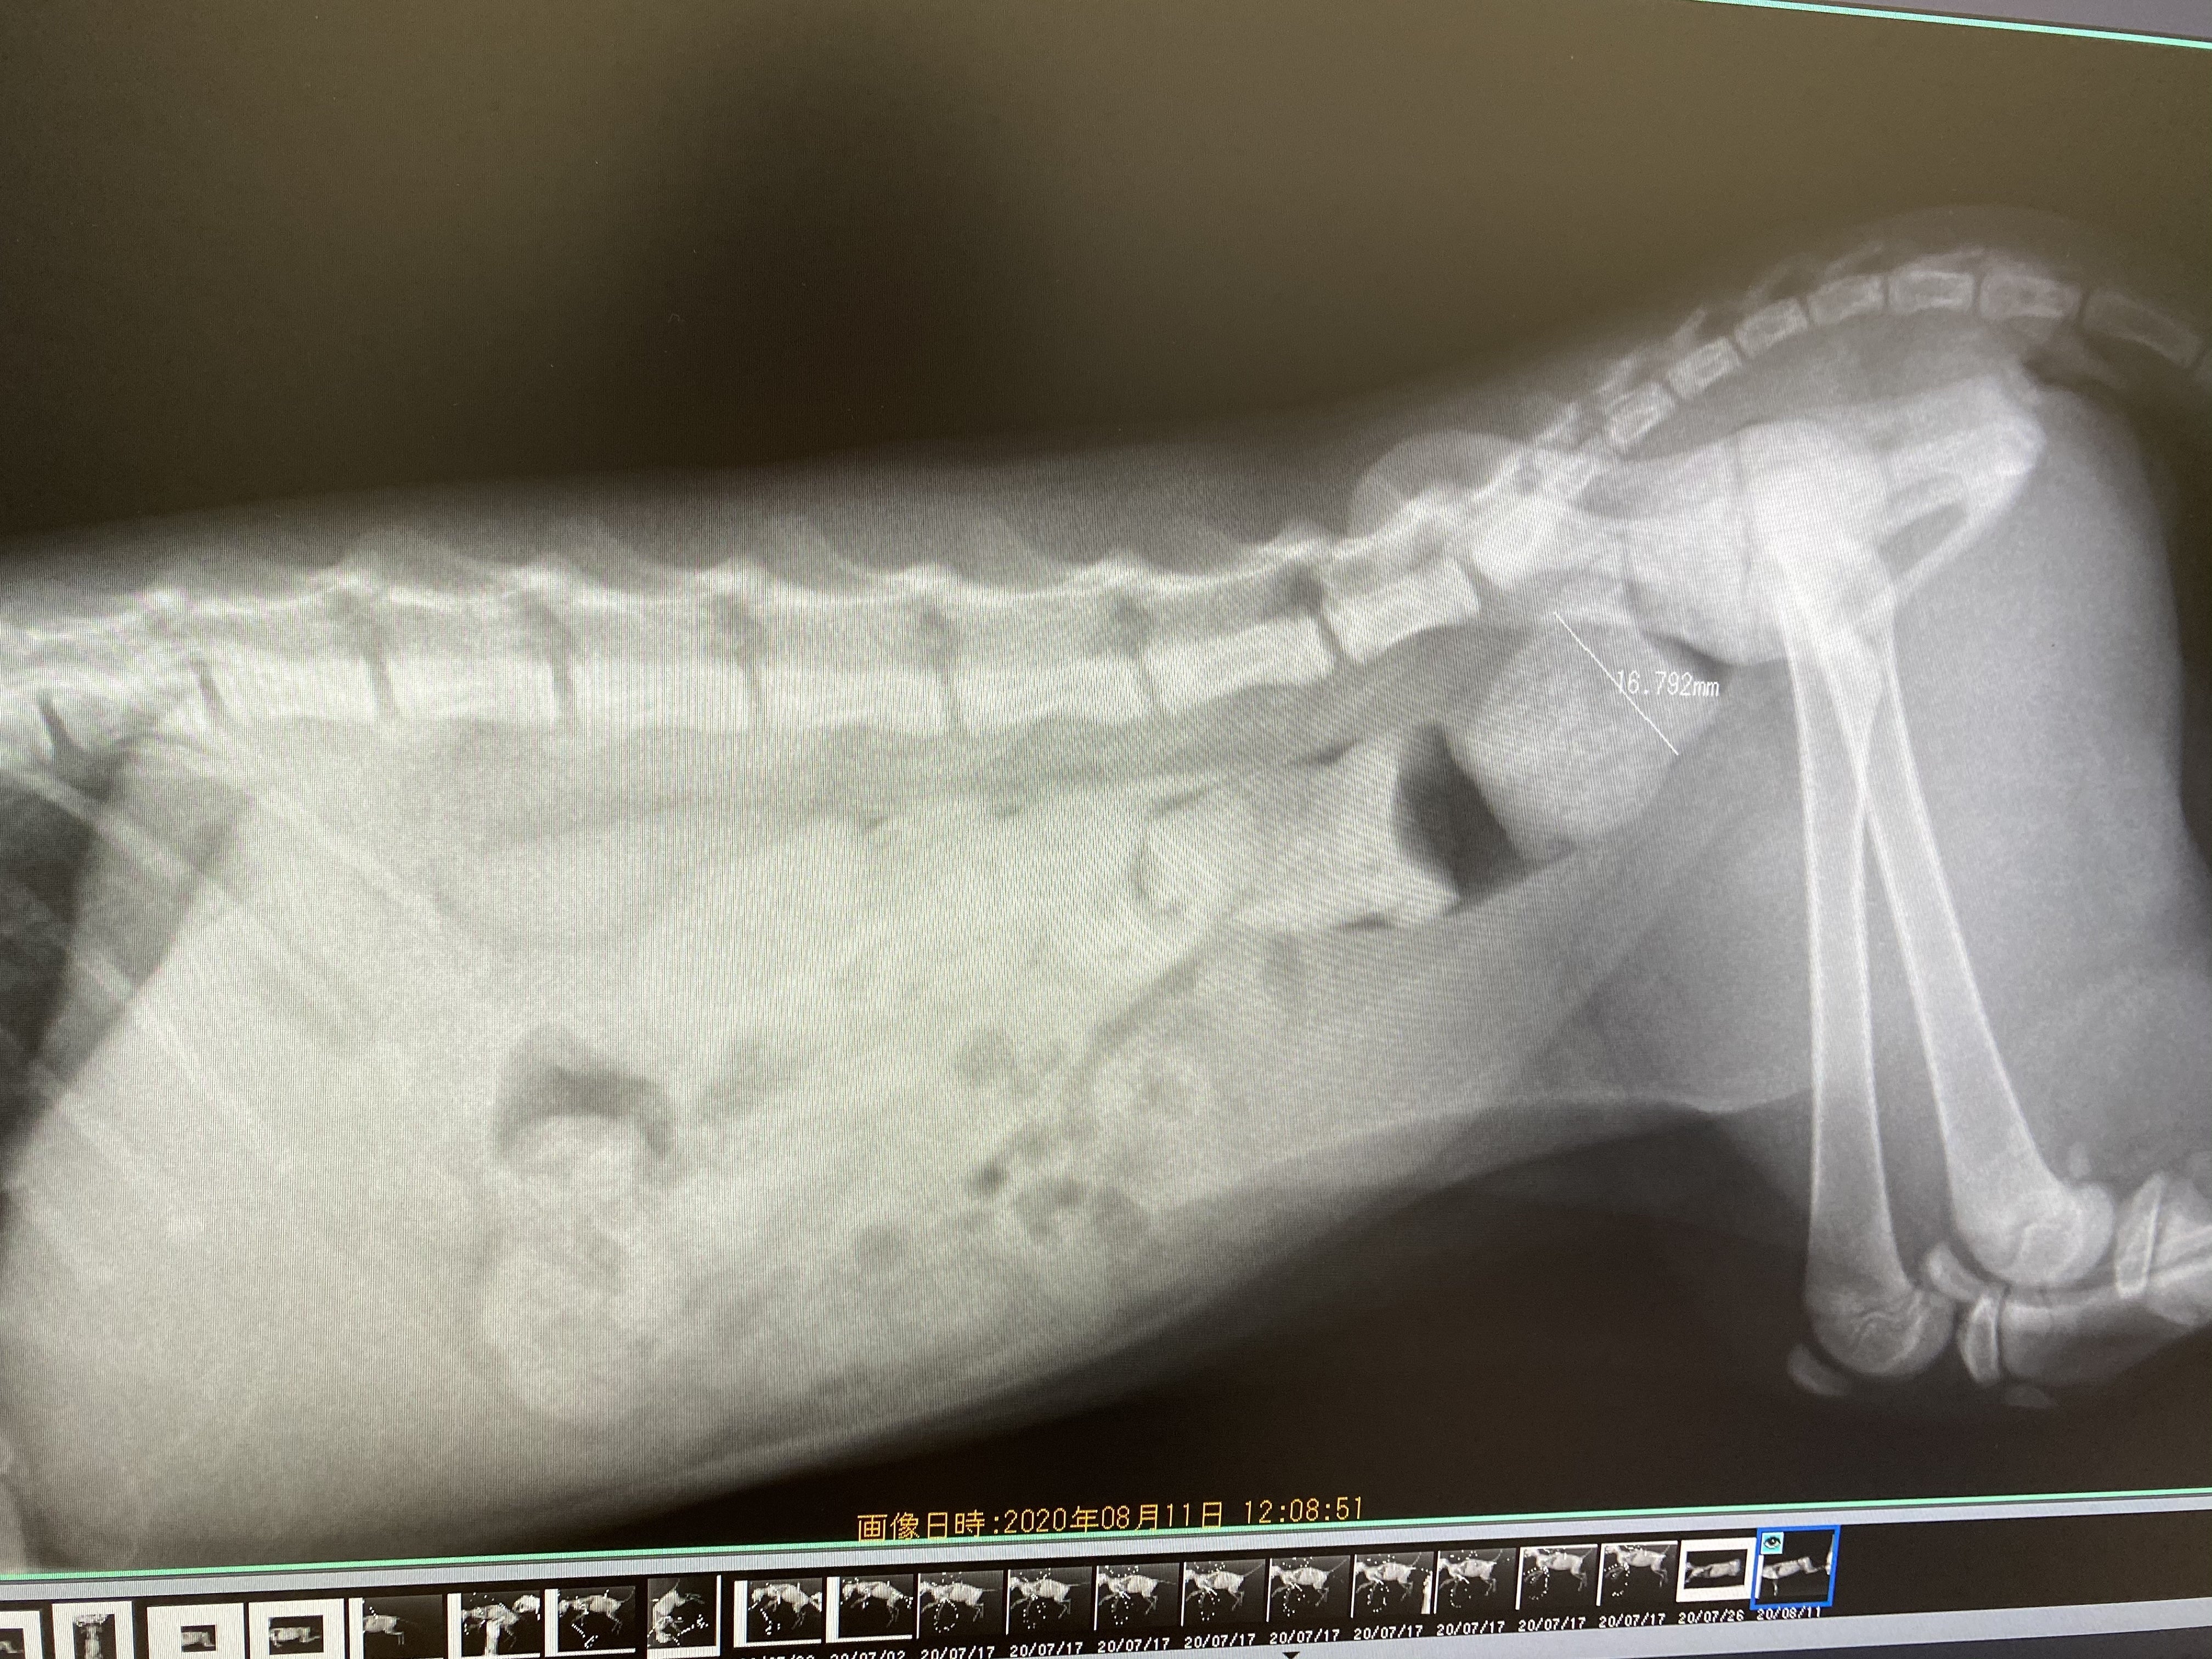

レントゲン撮影の結果、約16ミリの太さのうんちが詰まっていることがわかり、いまの肛門では排便困難だろうと主治医からご説明がありました。